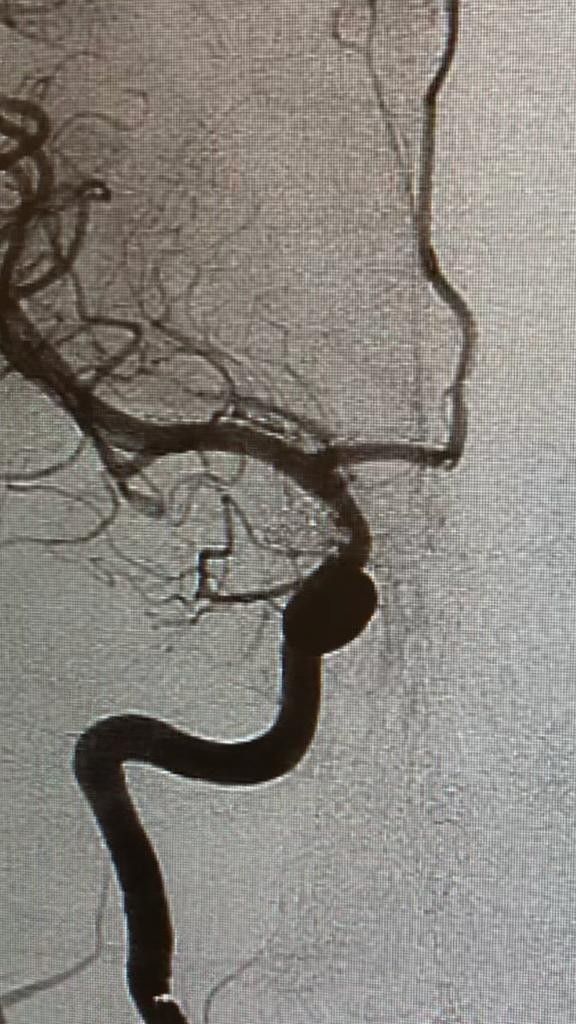

Kafatası açılmadan anevrizma operasyonu

Hastanın komada geldiğini anlatan Medicana International İzmir Hastanesi Beyin ve Sinir Cerrahı Doç. Dr. Özhan Merzuk Uçkun, "Hastanın ikinci bir beyin kanaması geçirme riski yüzde 50'ydi. Hazırlığımızı yaparak, gece 22.00'de ameliyata girdik. Kasıktan girilerek yaptığımız endovasküler cerrahiyle kanayan beyin damarının içine akıllı teller yerleştirdik ve kanamasını durdurduk. Ameliyattan da gece 01.00'de çıktık. Hastamız bir süre yoğun bakımda tedavi gördükten sonra servise çıktı. Şu an kendisi sağlıklı. Baloncuğun kanama riski binde 1-5 arasında. Bu tür beyin kanaması geçiren hastalarda zamanla bir yarış vardır. En kısa sürede hastaneye getirilerek tedavi altına alınmalıdır. Ne yazık ki beyin kanaması geçiren hastaların önemli bir kısmı, geç kalındığı için hayatını kaybedebiliyor" dedi.

Kafatası açılmadan anevrizma operasyonu

Hastanın komada geldiğini anlatan Medicana International İzmir Hastanesi Beyin ve Sinir Cerrahı Doç. Dr. Özhan Merzuk Uçkun, "Hastanın ikinci bir beyin kanaması geçirme riski yüzde 50'ydi. Hazırlığımızı yaparak, gece 22.00'de ameliyata girdik. Kasıktan girilerek yaptığımız endovasküler cerrahiyle kanayan beyin damarının içine akıllı teller yerleştirdik ve kanamasını durdurduk. Ameliyattan da gece 01.00'de çıktık. Hastamız bir süre yoğun bakımda tedavi gördükten sonra servise çıktı. Şu an kendisi sağlıklı. Baloncuğun kanama riski binde 1-5 arasında. Bu tür beyin kanaması geçiren hastalarda zamanla bir yarış vardır. En kısa sürede hastaneye getirilerek tedavi altına alınmalıdır. Ne yazık ki beyin kanaması geçiren hastaların önemli bir kısmı, geç kalındığı için hayatını kaybedebiliyor" dedi.